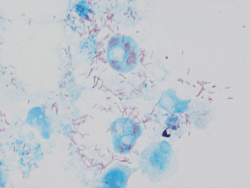

![]() Bacilos rojos intracelulares de Rickettsia conorii | ||

Rickettsia conorii es una bacteria del género Rickettsia, gramnegativa, parásito intracelular obligado que causa la fiebre botonosa mediterránea. Es transmitida por la picadura de la garrapata Rhipicephalus sanguineus, que a su vez la adquiere de los animales que parasita, generalmente cánidos, tanto domésticos como silvestres. Se extiende por el mar Mediterráneo, mar Negro, Israel, Kenia, India y otras regiones del norte, centro y sur de África.

Cocobacilo de pequeño tamaño y crecimiento intracelular obligatorio.